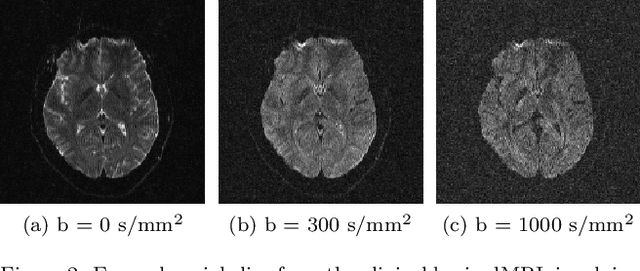

Abstract:We propose a novel approach to denoising diffusion magnetic resonance images (dMRI) using convolutional neural networks, that exploits the benefits of data acquired at multiple b-values to offset the need for many redundant observations. Denoising is especially relevant in dMRI since noise can have a deleterious impact on both quantification accuracy and image preprocessing. The most successful methods proposed to date, like Marchenko-Pastur Principal Component Analysis (MPPCA) denoising, are tailored to diffusion-weighting repeated for many encoding directions. They exploit high redundancy of the dataset that oversamples the diffusion-encoding direction space, since many directions have collinear components. However, there are many dMRI techniques that do not entail a large number of encoding directions or repetitions, and are therefore less suited to this approach. For example, clinical dMRI exams may include as few as three encoding directions, with low or negligible data redundancy across directions. Moreover, promising new dMRI approaches, like spherical b-tensor encoding (STE), benefit from high b-values while sensitizing the signal to diffusion along all directions in just a single shot. We introduce a convolutional neural network approach that we call multi-b-value-based denoising (MBD). MBD exploits the similarity in diffusion-weighted images (DWI) across different b-values but along the same diffusion encoding direction. It allows denoising of diffusion images with high noise variance while avoiding blurring, and using just a small number input images.